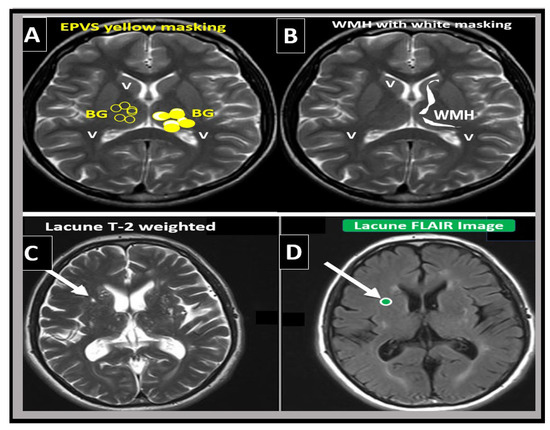

From a clinical standpoint, SVD presents and is associated with lacunar strokes that are responsible for at least 20% of ischemic strokes and represent a major cause of vascular cognitive impairment. Additionally, EPVS are known to be a biomarker and a feature of both SVD and vascular dementia (VaD), which are known to be associated with lacunar stroke as well as WMH [4,14,25,26,27]. Therefore, it is important to distinguish between lacunes, EPVS, and WMH as it pertains to SVD and strokes (Figure 5 and Figure 6).

Figure 6. Magnetic resonance imaging (MRI) comparison of enlarged perivascular spaces (EPVS), white matter hyperintensities (WMH), and lacunes. (A) depicts EPVS localized to the basal ganglia (symmetrical) with yellow color masking of EPVS (EPVS localized to centrum semiovale not shown). (B) depicts WMH localized to the periventricular regions (deep white matter WMH not shown). (C) depicts a T-2-weighted lacune (arrow). (D) depicts a FLAIR image with cyan color masking. Note the encircling white line to suggest hyperintensity FLAIR. V = ventricle.